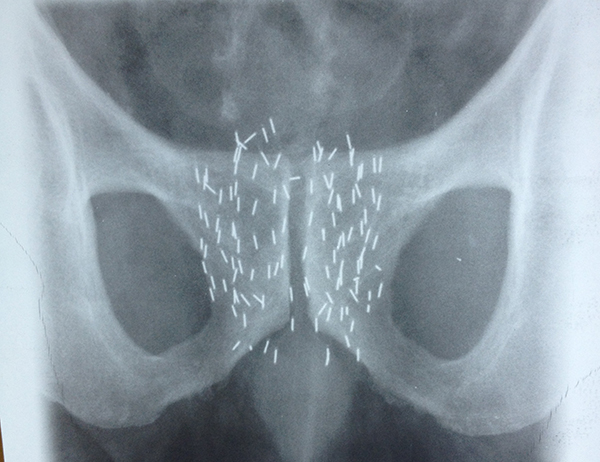

Braquiterapia de próstata: implante con semillas de yodo 131 realizado por el Dr. Nicholas Reñé

Para los tratamientos de Braquiterapia de próstata con semillas radiactivas de Iodo-125 se emplea un ecógrafo B&K dedicado con un transductor biplanar que permite obtener imágenes transversales (axiales) y longitudinales (sagitales) de la próstata.

El transductor ecográfico se monta sobre un aparato denominado Stepper. Esta disposición permite la guía estereotáctica de las agujas con las cuales se depositan las semillas de Iodo radiactivo en la próstata.

La braquiterapia prostática se realiza en quirófano, con el paciente en posición de litotomía (posicion ginecológica) y con anestesia espinal. Bajo guía ecográfica y radioscópica se procede a la colocación de agujas cargadas con semillas de I-125. Esas semillas se depositan de manera definitiva en la próstata y liberaran su energía tratando al tumor. Una vez agotada su energía permanecerán en la próstata sin que esto acarree ningún tipo de consecuencia. El procedimiento tiene una duración aproximada de 1,5 a 2 hs. El paciente obtiene el alta el mismo día, pudiendo incorporarse a sus rutinas diarias sin inconvenientes.